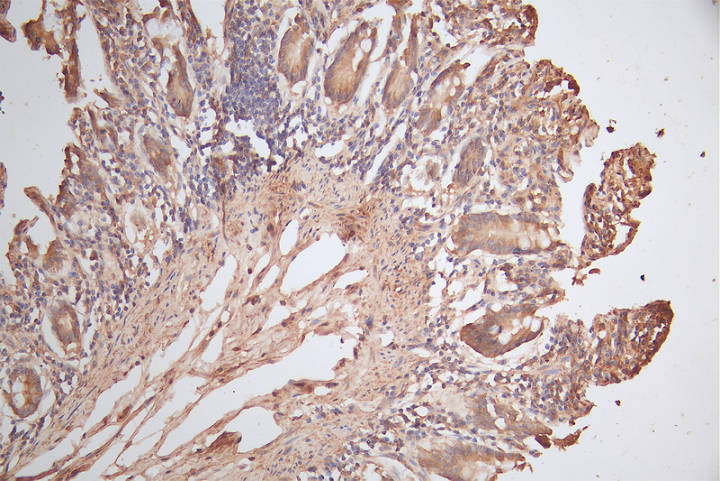

IHC image of CSB-PA010565LA01HU diluted at 1:150 and staining in paraffin-embedded human small intestine tissue performed on a Leica BondTM system. After dewaxing and hydration, antigen retrieval was mediated by high pressure in a citrate buffer (pH 6.0). Section was blocked with 10% normal goat serum 30min at RT. Then primary antibody (1% BSA) was incubated at 4°C overnight. The primary is detected by a biotinylated secondary antibody and visualized using an HRP conjugated SP system.

IHC image of CSB-PA010565LA01HU diluted at 1:150 and staining in paraffin-embedded human liver cancer performed on a Leica BondTM system. After dewaxing and hydration, antigen retrieval was mediated by high pressure in a citrate buffer (pH 6.0). Section was blocked with 10% normal goat serum 30min at RT. Then primary antibody (1% BSA) was incubated at 4°C overnight. The primary is detected by a biotinylated secondary antibody and visualized using an HRP conjugated SP system.